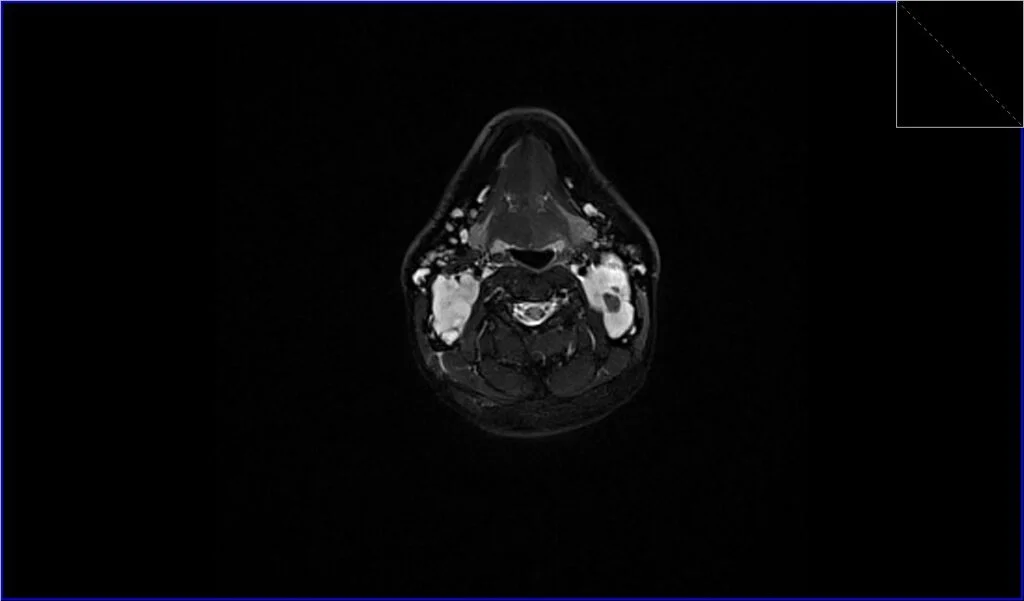

Short Tau Inversion Recovery (STIR) Images: STIR is an MRI sequence that is particularly sensitive to fluids and edema within tissues. Lymphomatous tissue will typically appear very bright on STIR images due to its high water content. The STIR sequence is also valuable in suppressing fat signal, making lymph nodes stand out more distinctly against the fatty background, which is common in areas like the neck.

STIR axial image shows Lymphoma